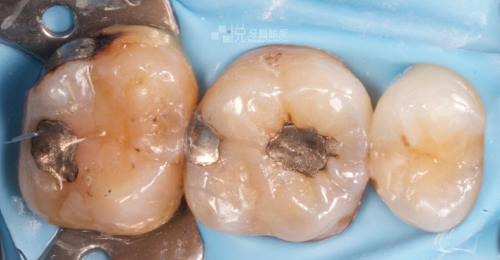

在麻藥退之後,有的人可能在活髓保存術後的前幾天會有酸酸、脹脹、怪怪的感覺屬正常現象,建議先避免吃太刺激食物(如:太冰、太燙、太酸等),讓牙齒休息一下、適應材料,若有不適可先服用醫師開立的藥物來緩解。

為了避免二次蛀牙所造成的牙髓感染及發炎,須維持口腔清潔(正確的刷牙、使用牙線),並且術後三個月及維持每半年定期回診追蹤,,醫生會視情況測試牙髓感受性(例如冰測試)或搭配X光來確認牙髓神經健康程度喔!

而當活髓保存術的牙齒常有結構上的缺損,建議搭配微創齒雕或假牙,保護牙齒避免斷裂、降低二度蛀牙的機率。